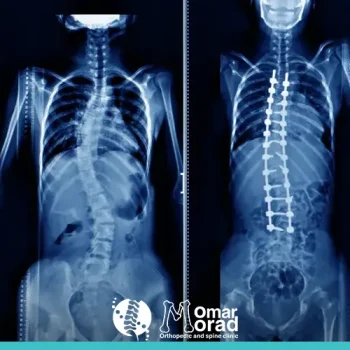

حالات اعوجاج العمود الفقري​

اعوجاج العمود الفقري اسفل الظهر